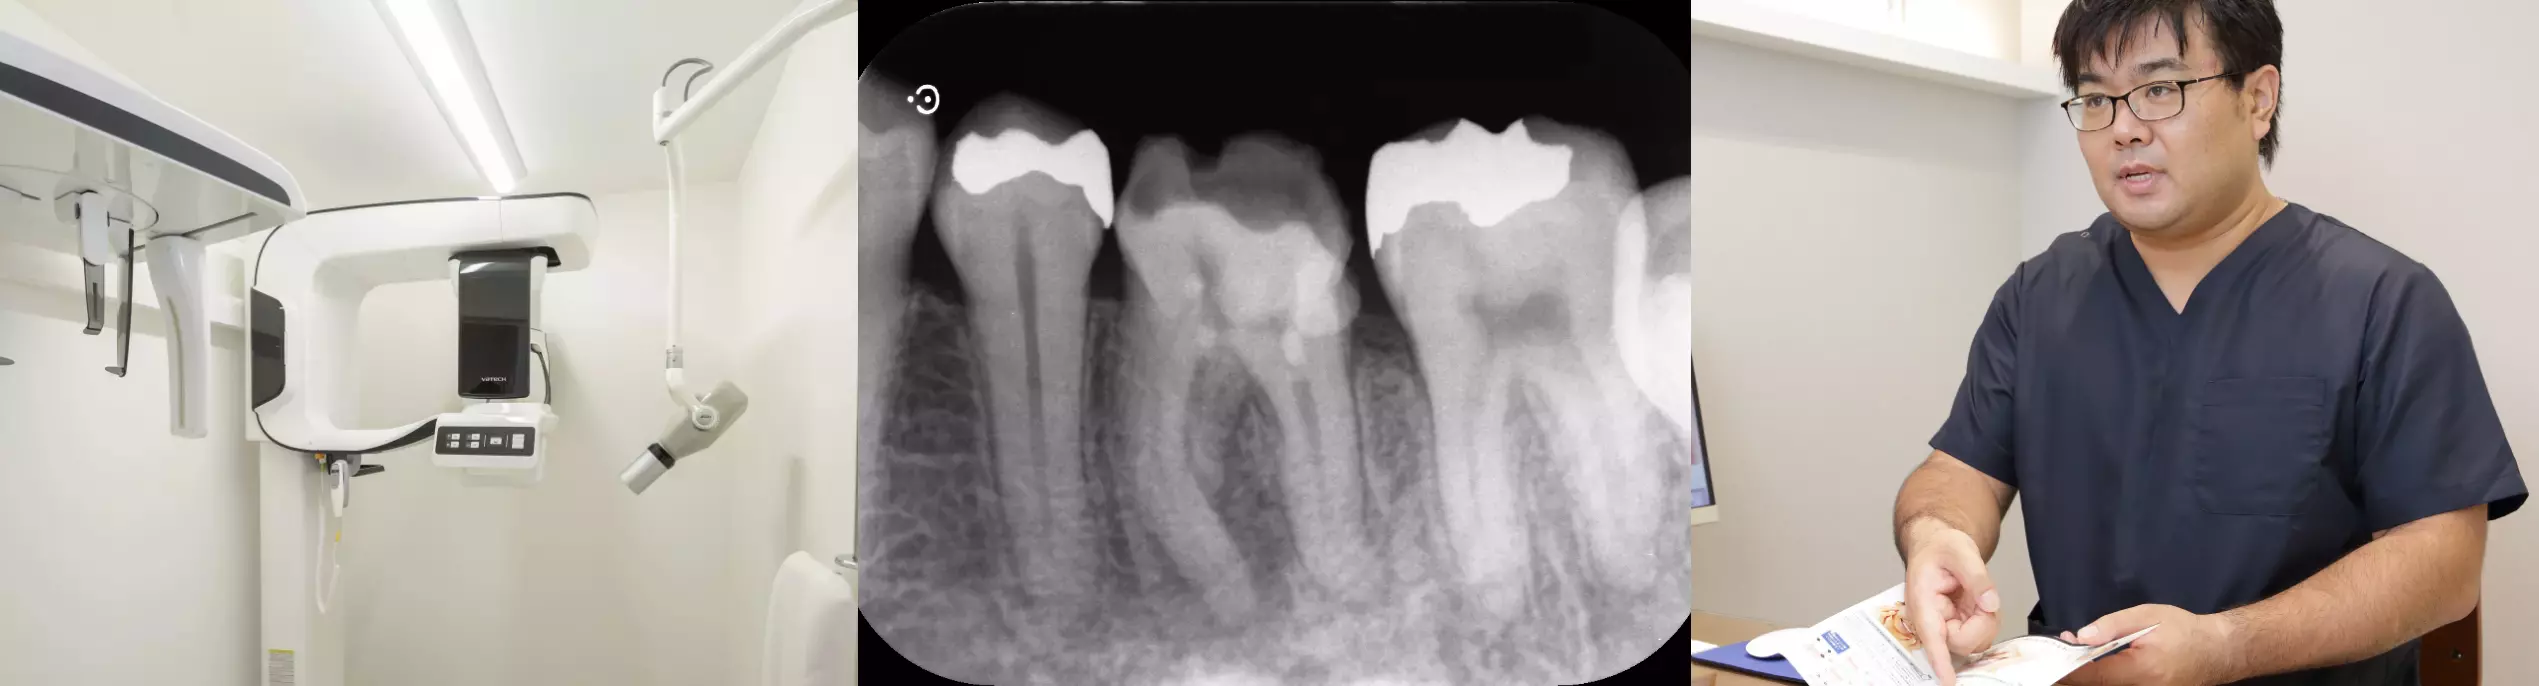

患歯となる歯を最新の歯科用CTによりパノラマX線写真、デンタルX線写真などで細かな部分まで特定し、歯髄や歯根の周囲の診断をいたします。症状の度合いから、専門医が今後の治療計画を綿密に提案・説明させていただきます。

そこで当院では、歯科用顕微鏡であるマイクロスコープで20倍以上に拡大した視野を確保しながら、精密な治療を行います。実際に根管の状態を見ながら治療しますので、根管治療よりも壊死した神経を見落とすことが少なくなり、結果的に成功率の大きな向上につながります。